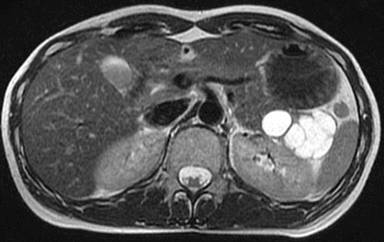

An asymptomatic, 37-year-old woman was admitted to our hospital for surgery. In 2006, she was determined to have two cystic lesions in the pancreatic tail, 15 and 13 mm in size, respectively. By 2012, these cystic lesions had grown to 40 and 20 mm in size, respectively. She had a history of mixed connective tissue disease and took 2 mg of prednisone per day. Blood chemistry and urinalysis were within normal limits. The tumor markers CA 19-9 (251 U/mL; reference range 0-37 U/mL) and SPAN-1 (38 U/mL; reference range 0-30 U/mL) were increased. Computed tomography showed a multilocular cyst, 40 mm in size, and a unilocular cyst, 20 mm in size, in the tail of the pancreas and gallstones. The cystic component was hypointense on T1-weighted magnetic resonance images and hyperintense on T2-weighted magnetic resonance images (Figure 1). On magnetic resonance cholangiopancreatography, these cysts did not connect with the main pancreatic duct and had no solid components. Fluorine-18fluorodeoxyglucose positron emission tomography (FDG-PET) showed no significant increase in the maximum standard uptake value. Suspecting a mucinous cystic neoplasm or an intraductal papillary mucinous neoplasm with gallstones, a laparoscopic distal pancreatectomy was performed. First, the spleen and the pancreatic tail were mobilized from the retroperitoneum using the four-port technique laparoscopically (Figure 2). After the mobilization, the splenic artery was identified, double clipped, and ligated. The splenic vein was also clipped and dissected. After access was achieved through the 5 cm suprapubic incision, the pancreatic tail and spleen including the two cystic lesions were transected with a linear stapler (Endo GIA Ultra Universal Stapler, 30 mm Black, Covidien, Dublin, Ireland) (Figure 3) and extracted from the peritoneal cavity. A cholecystectomy was also performed. The operative time was 278 min and the blood loss was 50 mL.

Figure 1. Magnetic resonance imaging showed a multilocular cyst, 40 mm in size, and a unilocular cyst, 20 mm in size, in the tail of the pancreas. |